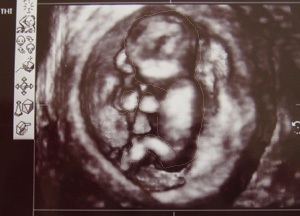

今回は3D画像。今までのは2D。

実際に見せて貰えるものやビデオの画像は黄色っぽいカラーでもっとリアルに見える。

でも今回は分かりませんでしたwwもっとこう足を広げてどかーっとしててくれればわかったのに(´・ω・`)いやべつにいんだけどね。まだレナの(女の子の)可能性も残っているからさ。楽しみは後の方がいいもんね。

それにしてもなんて赤ちゃんらしい可愛い格好なんだろう。顔の前に手をやって小さくなって寝てるわが子にもの凄い愛おしさを感じました。(でもこんな格好しているから他の角度のエコー写真は説明されたけど全然分からないww)

現在頭からお尻までの長さが9cmくらい。順調です。よかた。このままこのまま順調に育って!!